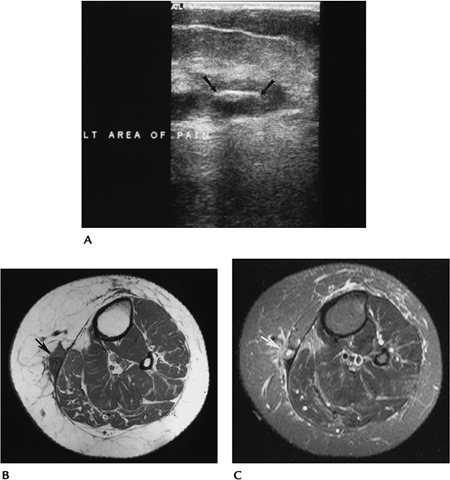

![]() |

FIGURE 11-10 Foreign body with infection. (A) Ultrasound demonstrates a wooden foreign body (arrows) in the thigh. Axial T1- (B) and contrast-enhanced fat-suppressed T1-weighted (C) images demonstrate adjacent soft tissue inflammation (arrow).